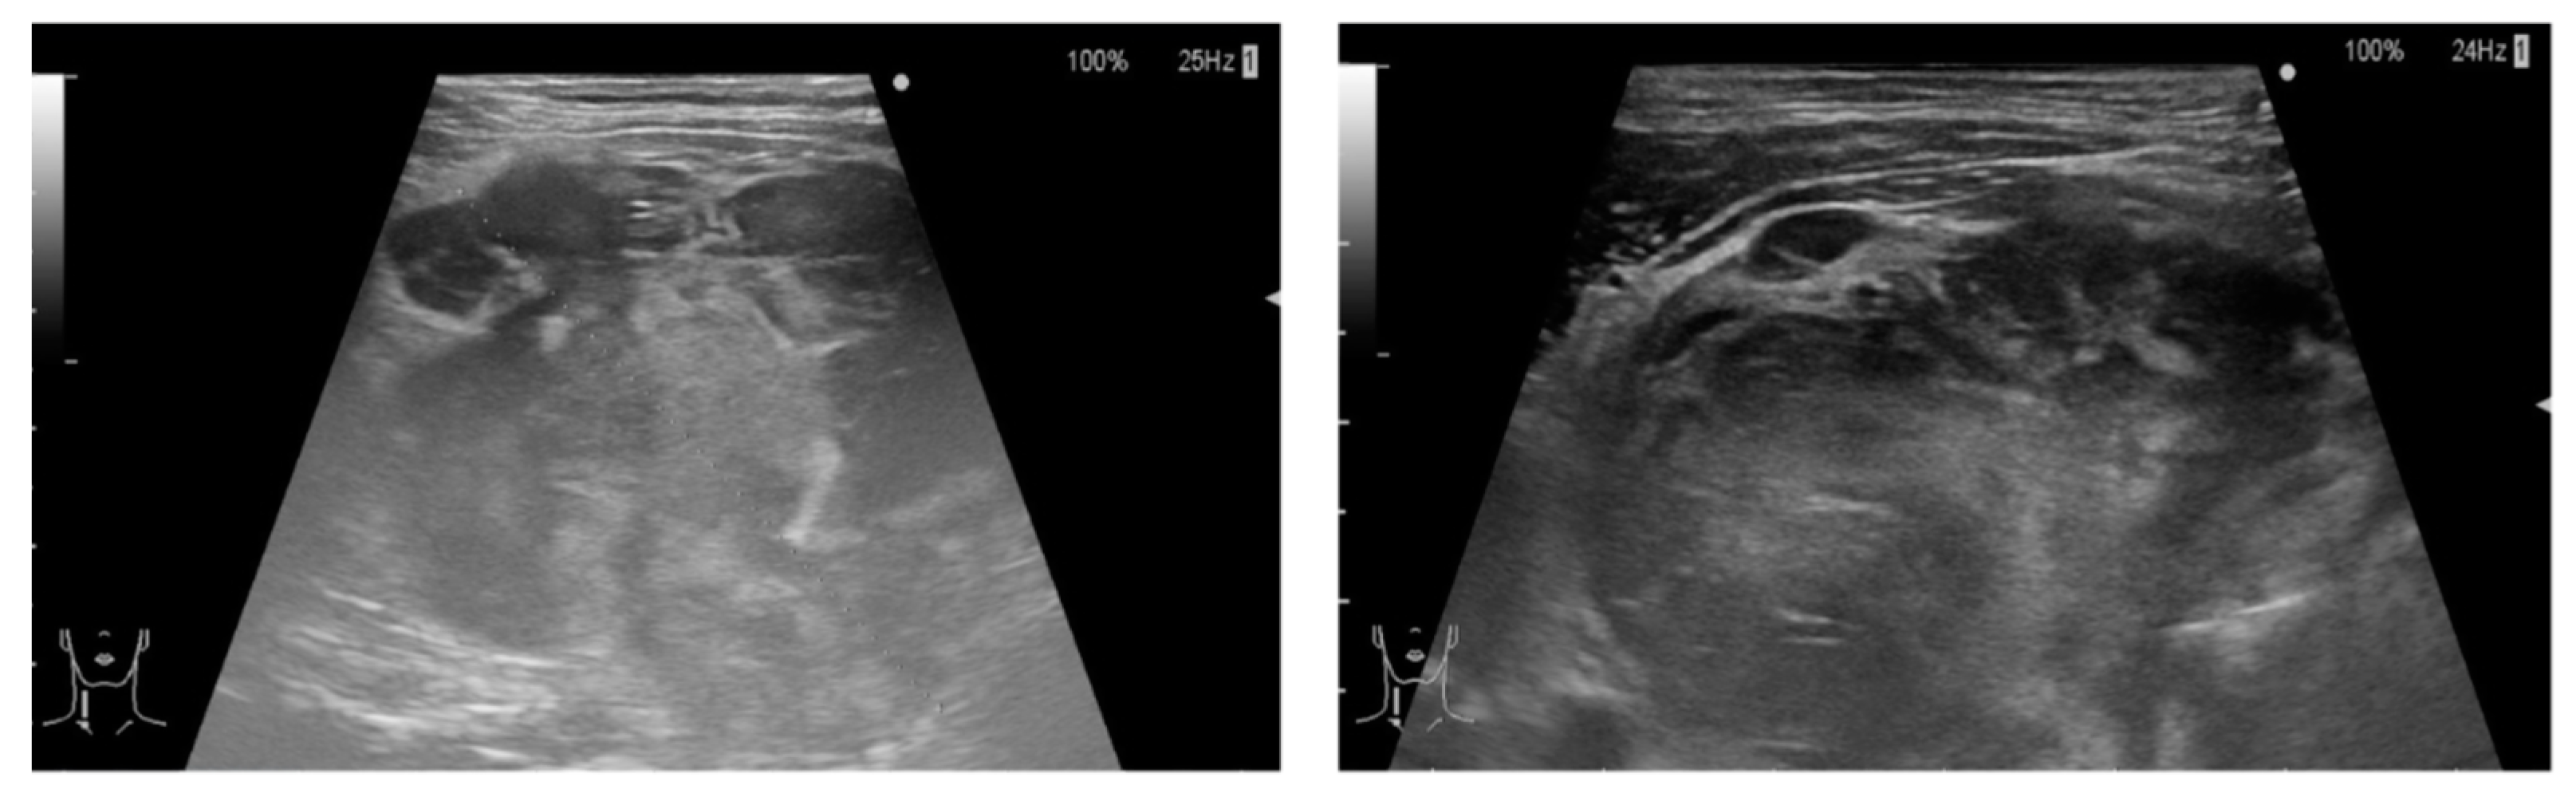

2. Case Report